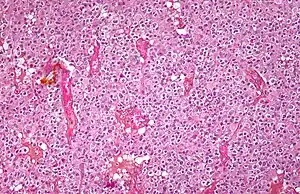

| Micrograph of an oligodendroglioma showing the characteristic branching, small, chicken wire-like blood vessels and fried egg-like cells, with clear cytoplasm and well-defined cell borders. H&E stain. | |

Oligodendrogliomas cannot currently be differentiated from other brain lesions solely by their clinical or radiographic appearance. As such, a brain biopsy is the only method of definitive diagnosis. Oligodendrogliomas recapitulate the appearance of the normal resident oligodendroglia of the brain. (Their name derives from the Greek roots 'oligo' meaning "few" and 'dendro' meaning "trees".) They are generally composed of cells with small to slightly enlarged round nuclei with dark, compact nuclei and a small amount of eosinophilic cytoplasm. They are often referred to as "fried egg" cells due to their histologic appearance. They appear as a monotonous population of mildly enlarged round cells infiltrating normal brain parenchyma and producing vague nodules. Although the tumor may appear to be vaguely circumscribed, it is by definition a diffusely infiltrating tumor.[6]

Classically they tend to have a vasculature of finely branching capillaries that may take on a "chicken wire" appearance. When invading grey matter structures such as cortex, the neoplastic oligodendrocytes tend to cluster around neurons exhibiting a phenomenon referred to as "perineuronal satellitosis". Oligodendrogliomas may invade preferentially around vessels or under the pial surface of the brain.[6]